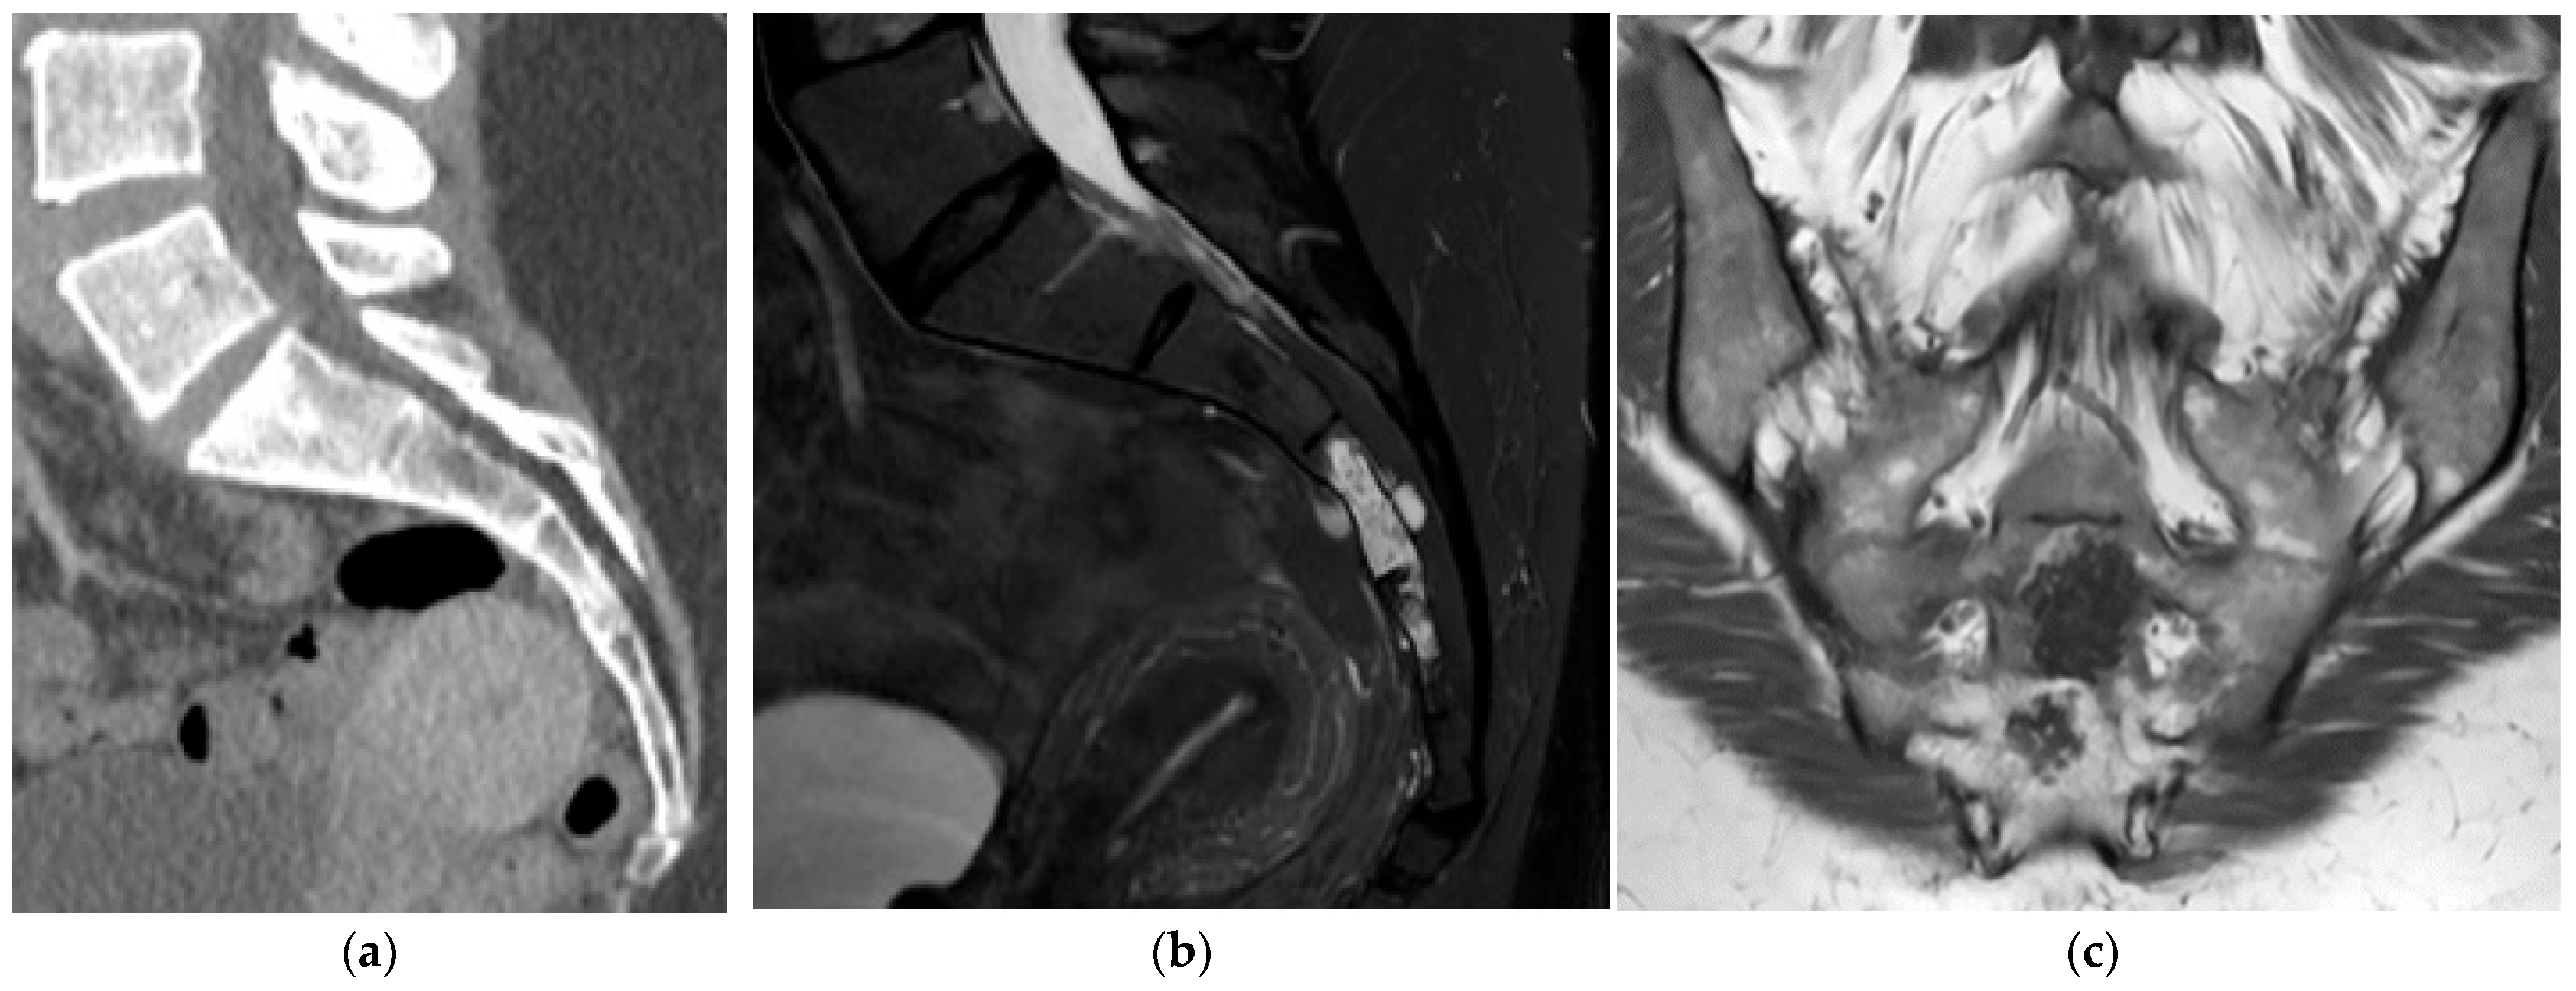

Ewing Sarcoma